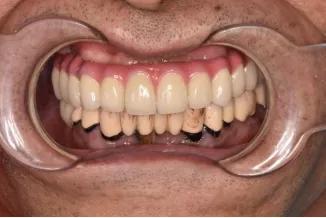

上面牙齒做了烤瓷橋冠,有根尖炎還缺了好幾顆牙

因為我上半口的牙已經(jīng)在朋友那里拔掉了,就先給我種植上半口,采用的“牙立得”技術(shù),當天種牙就當天可以戴上臨時的牙,看起來不會丑

這個方案很是滿意,之前做的牙冠橋先用著,省錢省力,性價比很高